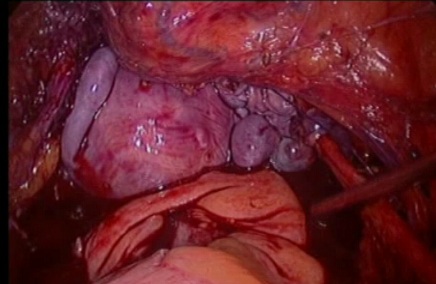

Till a few decades ago, the presence of cancer was considered as a contraindication to endoscopic surgery. However, with rapid advances in instrumentation and recognition of the multiple benefits of endoscopy, endoscopic surgery has become an acceptable modality of treatment for select cancers.

The two gynecological cancers ideally suited for endoscopic treatment are endometrial and cervical cancer.